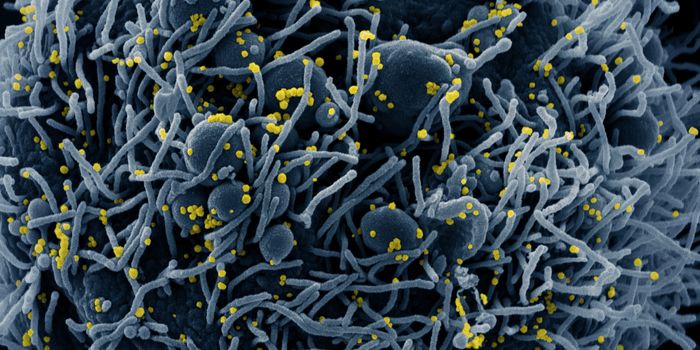

AUG 19, 2020Cell & Molecular BiologyAs the pandemic virus, SARS-CoV-2 continues to cause tens of thousands of new cases of COVID-19 every day in the United ...

APR 27, 2020MicrobiologyThe pandemic virus that causes COVID-19 has now infected nearly 3 million people, and killed over 200,000.